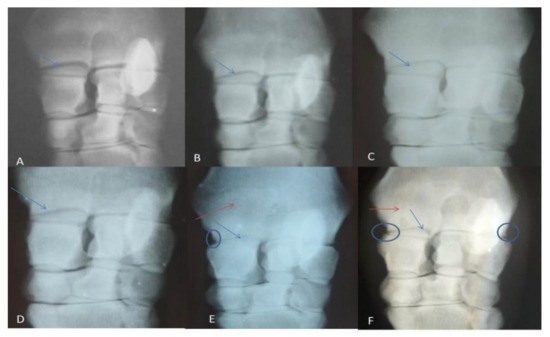

Radiographical findings revealed, according to OARSI:(1) joint space narrowing, which began to appear at the first month post-induction (grade 1), then gradually increased to be grade 2 at the second and third months, and reached grade 3 by the seventh month; (2) subchondral bone sclerosis, which began to appear from the third month post-injection, until the end of the experiment; (3) marginal osteophytes were observed in the fifth and seventh months, while bone attrition was not observed in the present study (Figure 1 and Table 2).

Figure 1. Showing radiographic grading: (A) normal (Day 0), (B) after one month of induction, (C) after 2 months, (D)after 3 months, (E)after 5 months, (F) After 7 months. The radio-carpal joint space showed gradual narrowing (blue arrows), subchondral bone sclerosis (red arrows) and osteophyte appeared in late stages (circle).

Radiographically, the gradual narrowing in the joint space, subchondral bone sclerosis, and osteophytes formation that were recorded in the current study agreed with the previous report [34]. Rat hips injected with MIA showed definite joint space narrowing and deformity of the femoral head, evidenced by a flattened epiphysis [56]. However, radiographical grading for the severity of OA in humans usually does not reflect the amount of inflammation and joint damage, therefore it does not correlate to joint pain [57,58]. These findings appeared sound to our findings; by the disease progress, the radiographic osteoarthritic changes were detected, and the lameness score decreased. Bone attrition was not observed in this study, which could be due to the dose of MIA injected, which resulted in mild to moderate osteoarthritic lesions.